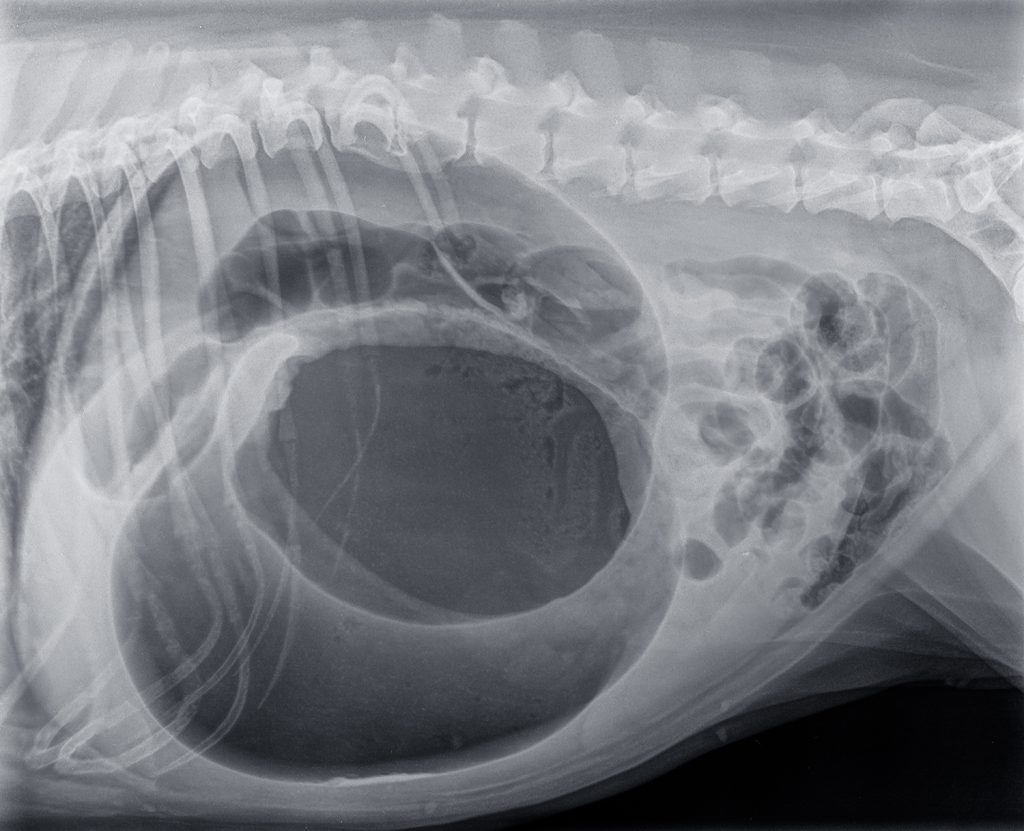

Diagnostiek

Bij een typisch beeld van de hiervoor genoemd signalement en verschijnselen, kan de diagnose vaak snel gesteld worden. Bij ernstige twijfel kunnen röntgenfoto’s van de buik gemaakt worden, dit geeft echter wel vertraging in de behandeling.